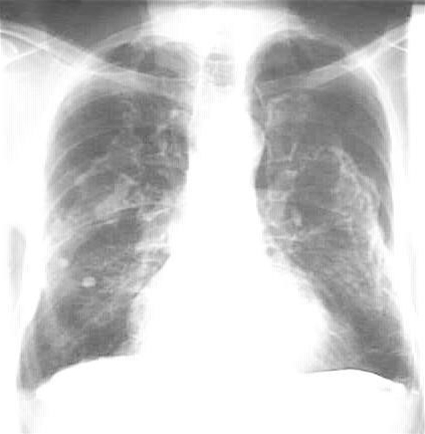

Asbestpåvirkning af lungerne: typiske dobbeltsidige lungehindeforkalkninger (pleurale plaques).